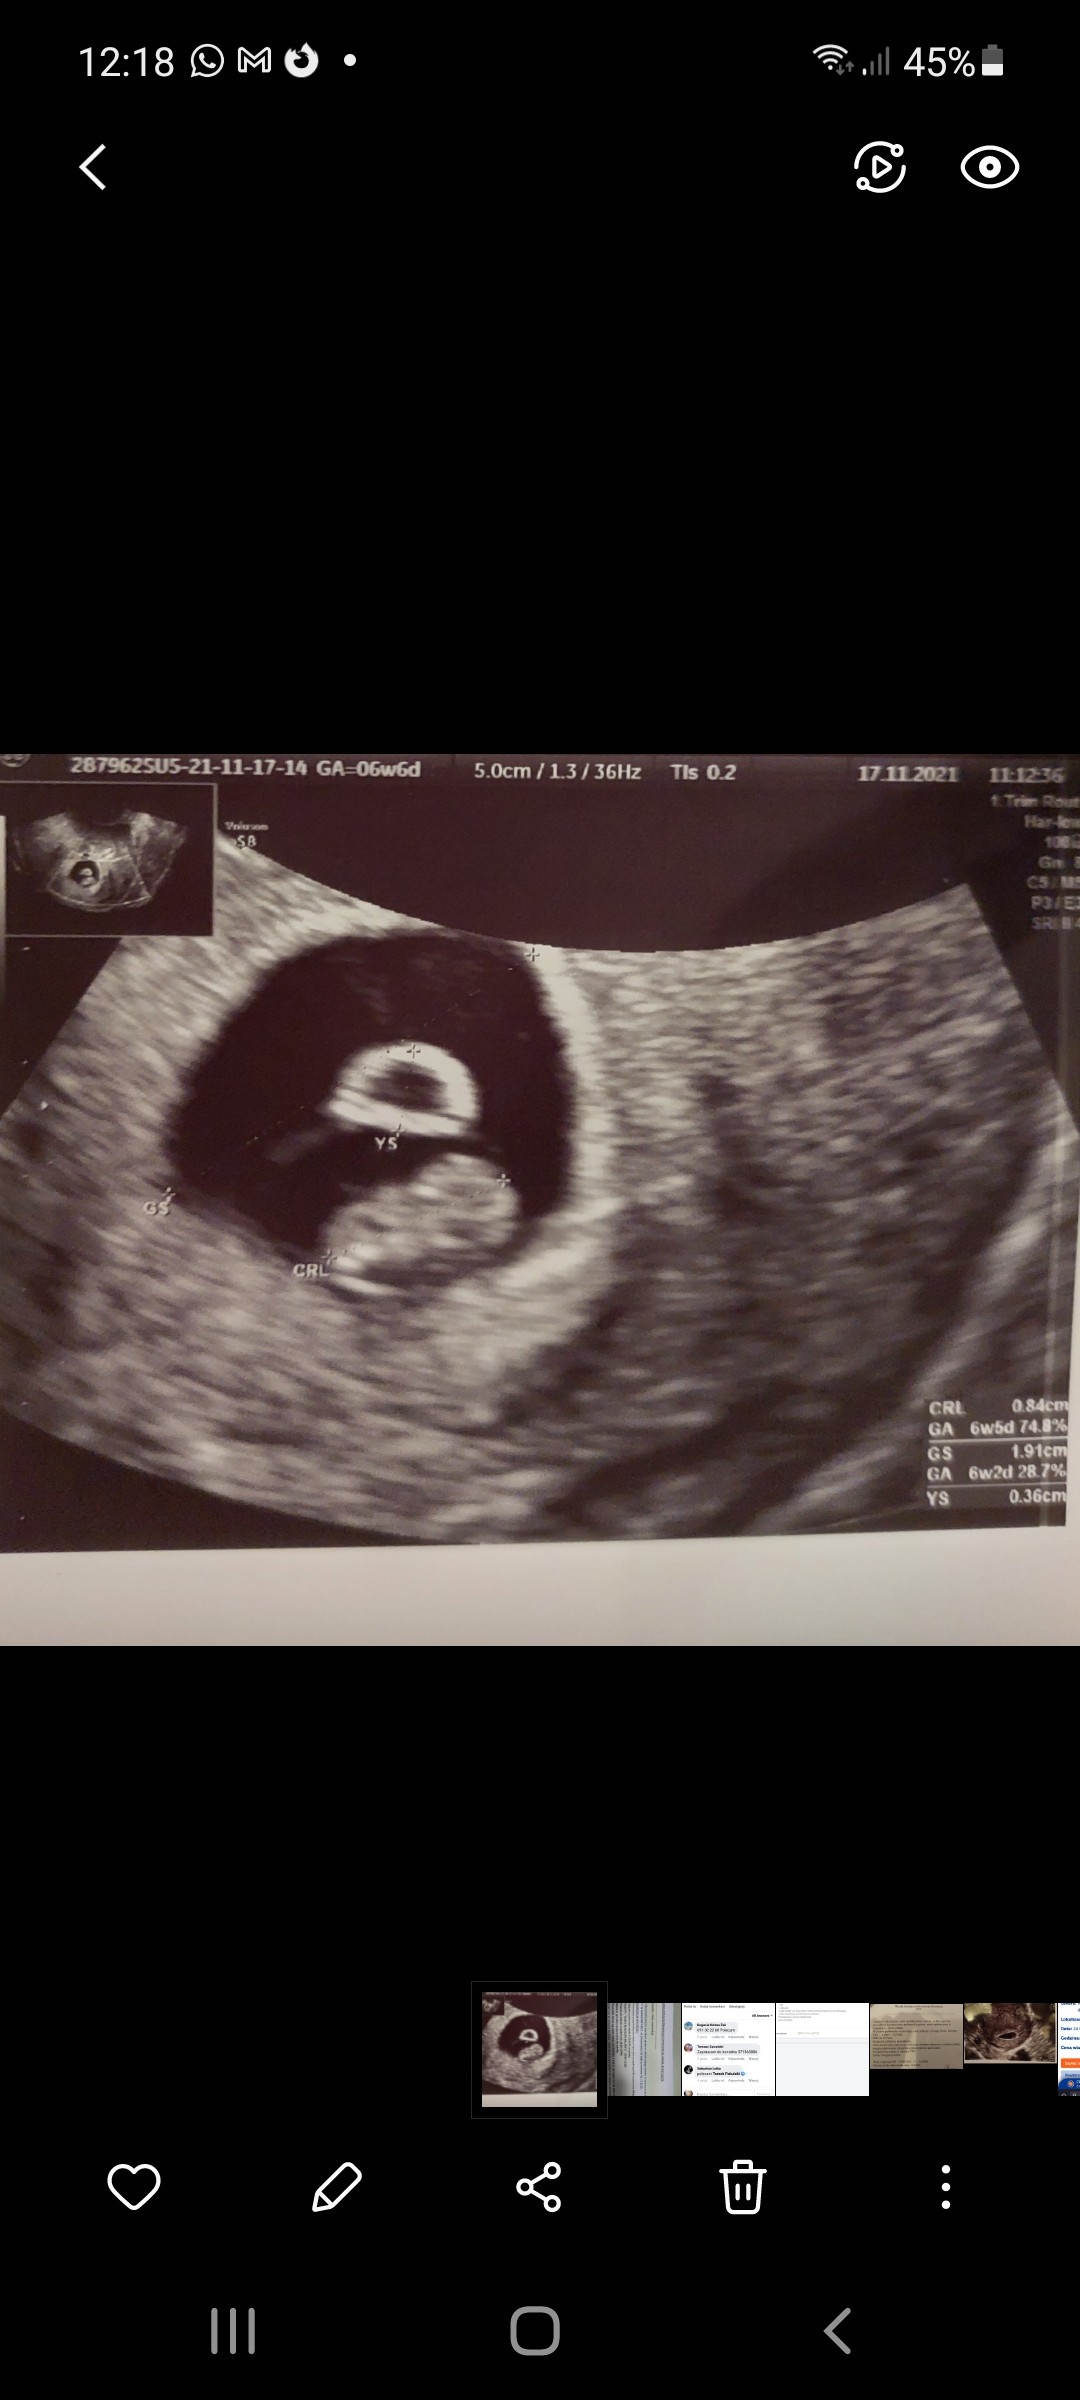

Ja jestem już po wizycie. Serduszko nadal bije. Wg Pani doktor w dobrym tempie, prawidłowo. Pęcherzyk okrąglutki tym razem, więc leżenie pomogło. Dostałam wreszcie kartę ciąży. Na 27.12 jestem umówiona na badania prenatalne

Kolejna wizyta za 2 tygodnie.